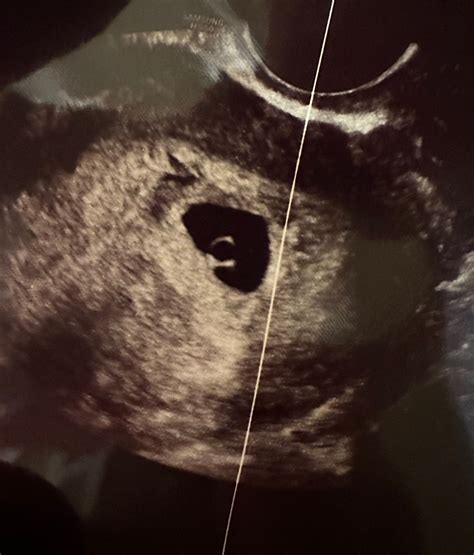

At 6 weeks, the embryo is still very small, measuring about 4-5 millimeters in length. The 6-week sonogram pictures will reveal several key features:

• Gestational Sac: This is the first structure visible on the ultrasound, appearing as a small, fluid-filled sac within the uterus.

• Yolk Sac: A small, round structure within the gestational sac that provides early nutrition to the embryo.

• Embryo: The actual embryo, which may be visible as a tiny, curved structure within the gestational sac.

• Fetal Pole: A thickened area within the embryo that will eventually develop into the fetus.

• Heartbeat: In some cases, a flickering heartbeat may be visible, indicating that the embryo is developing normally.

It’s important to note that the visibility of these structures can vary depending on the position of the embryo and the clarity of the ultrasound images. If the embryo is not clearly visible, the technician may recommend a follow-up ultrasound in a week or two.